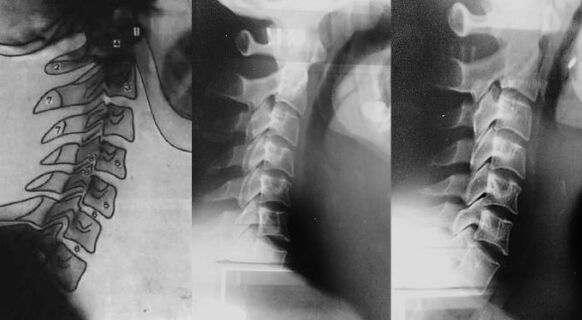

Az MRI képein az eltolódott első nyaki csigolya (a bal oldalon kép) látható; Könnyű foltok (a jobb oldali képen) jelölik Atlanta oldalsó tömegét; Az aszimmetria azt mondja, hogy a csigolya

Ennek ellenére a szülés során kapott sérülés nem mindig látható gyermekkorból, és csak érettségben érinti a beteget. Itt van egy példa. Az alábbiakban az X -Gray -n láthatja a nyaki gerinc normál kanyarját - kissé előre.

A beteg nyaka az első nyaki csigolya elmozdulásával. Nyilvánvaló, hogy a nyakban nem csak egy fényhajlítás van előre, hanem kissé ívelt, vagyis ebben az állapotban nem igazodik a terhelés helyes eloszlásához. A beteget diagnosztizálták a méhnyak régió osteokondrózisával.

A jobb oldalon ugyanazon beteg x -srája látható néhány hónappal az Atlastherapie után - a nyak elkezdi megszerezni a helyes kanyarot. Helyreáll.